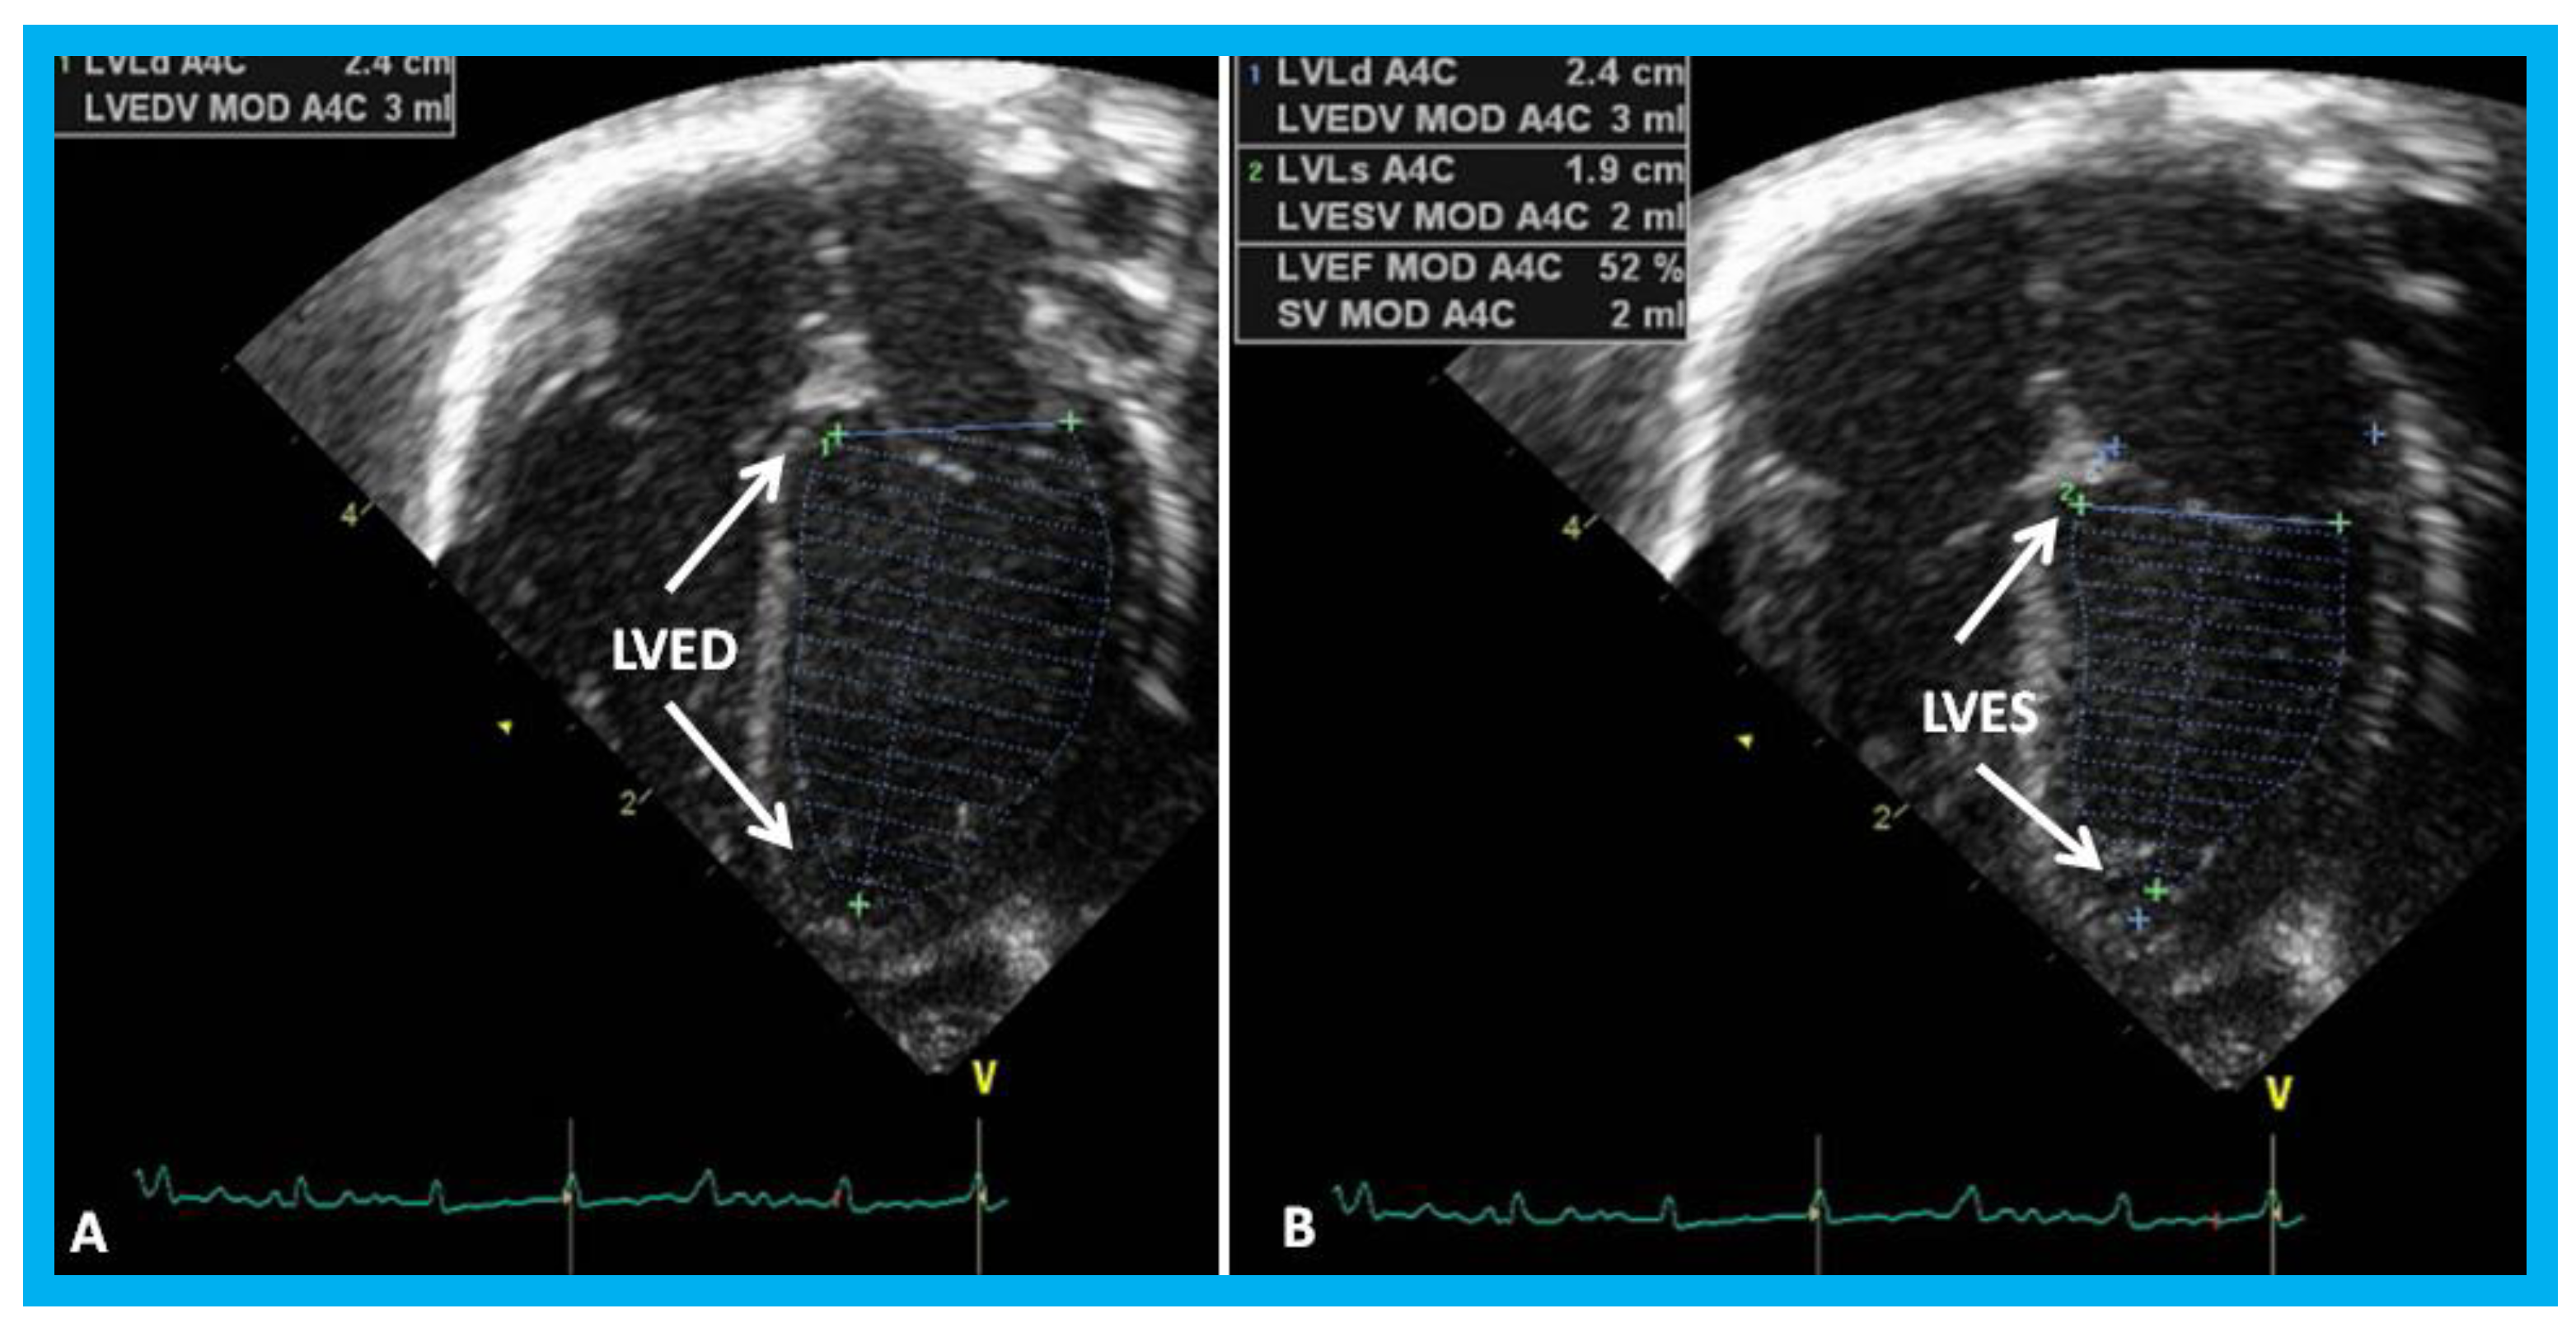

Figure 24. Apical four-chamber views of the left ventricle (LV) in end-diastole (LVED) in (A) and end-systole (LVES) in (B) demonstrating calculation of area shortening of the LV using Simpson’s rule: AS = (LVAd − LVAs)/LVAd (where AS is area shortening, LVAd is LV area in diastole, and LVAs is LV area in systole). The LV area shortening is 52% (see insert in (B)); normal values are 40 to 60%.